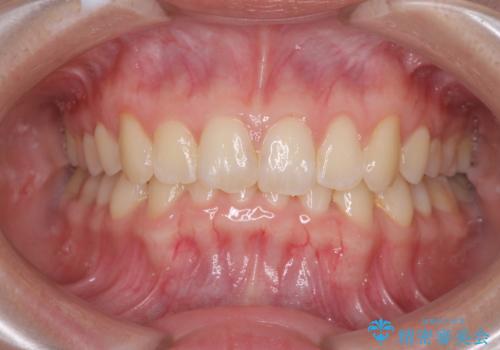

デコボコと深い咬み合わせの改善 インビザラインによる矯正治療

インビザラインによる前歯の矯正治療